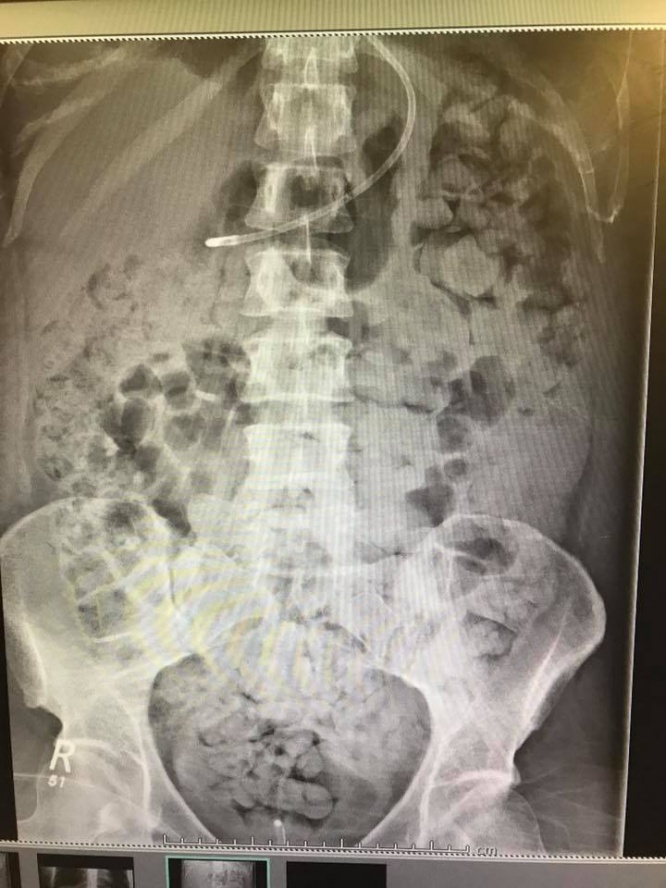

大便は胃を逆流して食道を通り口から出たものと思われる。病院では彼女の状態を確認するためにX線撮影をしたが、体中が大便と小便でいっぱいだったため臓器の確認が不可能だった。